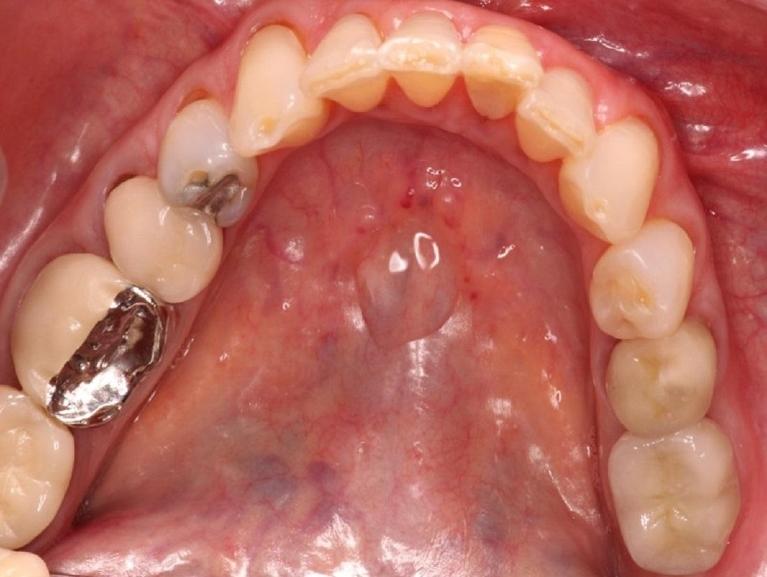

Dr. Uhl places the implant in the jawbone using a small titanium post that replaces the root of your missing tooth. Over time, the implant bonds with surrounding bone and tissue. This forms a secure foundation for the dental crown that Dr. Uhl eventually places over it. Dental implants can be used to replace one or more missing teeth, hold a dental bridge in place, secure a loose denture, or replace dentures with a permanent, fixed solution.

Made of biocompatible titanium, the implant post is placed surgically in your gum and allowed to heal throughout several months. During this time, the implant fuses fully with surrounding bone and tissue. After healing, Dr. Uhl attaches a porcelain crown to it that restores your appearance and allows you to eat, speak, and smile comfortably and with confidence.